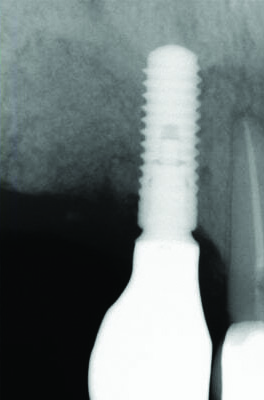

Fig 12. Case 2: Immediate postoperative radiograph. Note the tack securing the collagen membrane (upper left portion of the image).

The patient in case 2 received a crestal incision with full-thickness flap elevation, then tooth No. 5 was extracted (Figure 9). Implant debridement followed the same protocol used in case 1. FDBA was mixed with a small amount of doxycycline and placed around the implant (Figure 10). A resorbable collagen membrane (not pictured) was secured with a tack. Primary closure was achieved with expanded polytetrafluoroethylene (ePTFE) sutures (Figure 11). An immediate post-surgical radiograph showed bone fill and the tack (Figure 12).

The 12-month and 7-year follow-ups for case 2 showed similar improvements with normal soft-tissue healing and bone fill and normal pocket depths at 12 months (Figure 15 and Figure 16) and 7 years post-treatment (Figure 17 and Figure 18) (Table 1).